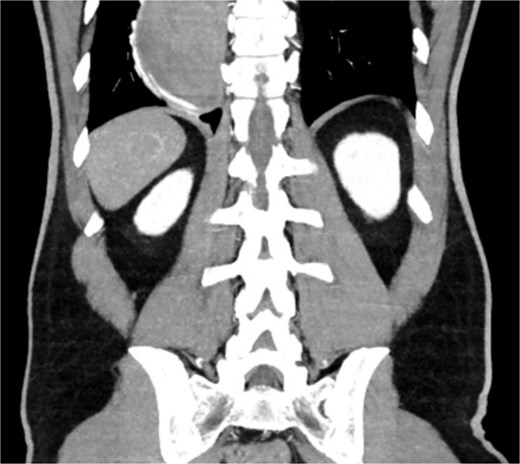

A 46-year-old male with a history of achalasia, for which he had undergone Heller myotomy with Nissen fundoplication in 2015, presented to the emergency department with a 2-day history of weakness and hematemesis. On admission, laboratory investigations revealed a significant drop in hemoglobin to 5 g/dl. Vital signs demonstrated tachycardia (122 beats per minute) and hypotension (70/50 mmHg), consistent with hemorrhagic shock. Initial management included aggressive resuscitation. Emergent gastroscopy was performed, which revealed the stomach filled with blood but failed to identify a clear bleeding source (Fig. 1). The patient remained hemodynamically unstable, necessitating transfusion of additional blood products. A computed tomography angiography was subsequently performed, revealing a markedly dilated, sigmoid-shaped esophagus, likely a sequela of end-stage achalasia. Furthermore, a contrast blush in the region of the distal esophagus, consistent with active ongoing bleeding (Fig. 2). An initial attempt was made to control the bleeding through angioembolization; however, this attempt was unsuccessful.

CT scan showing a markedly dilated esophagus with contrast blush in the distal third.